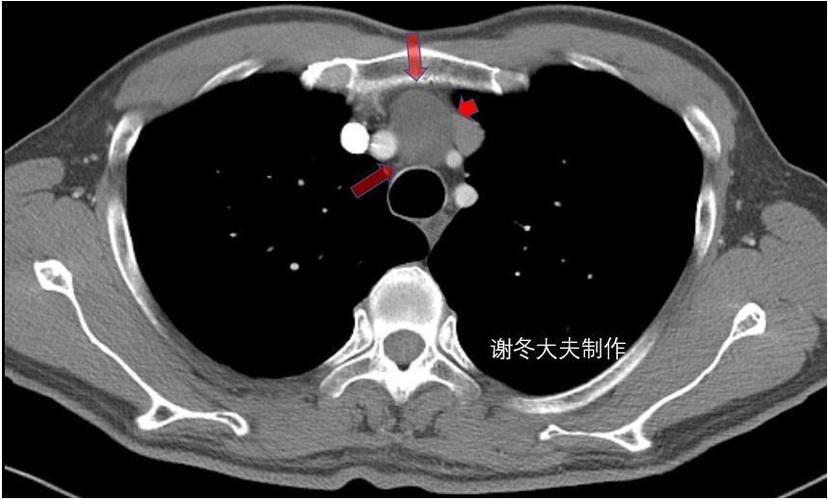

胸腺瘤前纵隔占位前纵隔结节是癌症吗

胸腺瘤/前纵隔占位/前纵隔结节/伴有肌无力是癌症吗?

省立影像读片前纵隔肿瘤2109